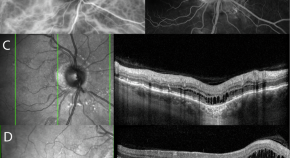

The seminal work of Wennberg and Gittelsohn in 1973 emphasised the importance of health information for informed decision-making. This led to the creation of the Dartmouth Health Atlas in 1996, which has become an important resource for monitoring health services in the USA. The Dartmouth Health Atlas research revealed the existence of variation in health care without benefit to patients, and the dependence of health care use on local resource supply. Similar initiatives emerged around the world, from the UK to Asia. The availability of administrative data has become essential for evaluating health service delivery and for informing health economic analysis and policy decisions. Access to data depends on the organisation of the health system, with more centralised systems facilitating comprehensive data collection. We contrast the decentralised structure of the Swiss healthcare system with that of the US and the UK, and highlight the challenges of harmonising data for nationwide health monitoring. The example of optical coherence tomography (OCT) in Swiss ophthalmology illustrates the variability in care practices and billing patterns. This variability can be attributed to the lack of clear guidelines and the complexity of billing codes. Incentives to charge incorrect rates influence billing, adding a further variance component to the variance in care that cannot be subtracted from the total variance at the level of a health insurance fund and distorting the results. In certain environments the quality of data on care is so variable that a sound conclusions for health policy decisions represent a great challenge.